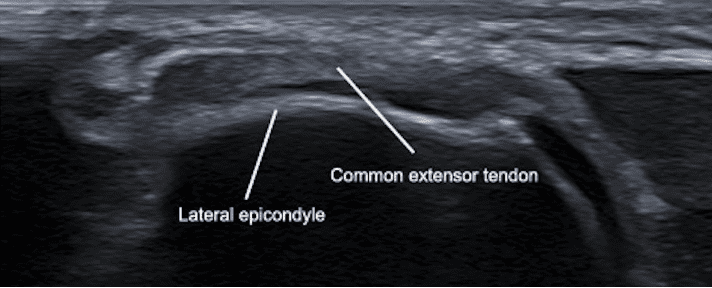

- Longitudinal View: Align the probe parallel to the long axis of the lateral epicondyle and extensor tendons. This view highlights the fibrillar structure of the tendons.

Figure 6. Ultrasound image of lateral elbow highlighting the common extensor tendon fibrillar structure in longitudinal view.

- Lateral Epicondyle: Visualized as a hyperechoic cortical surface, serving as the bony attachment site for extensor tendons.

- Common Extensor Tendon: Appears as a fibrillar, hyperechoic structure originating from the lateral epicondyle.